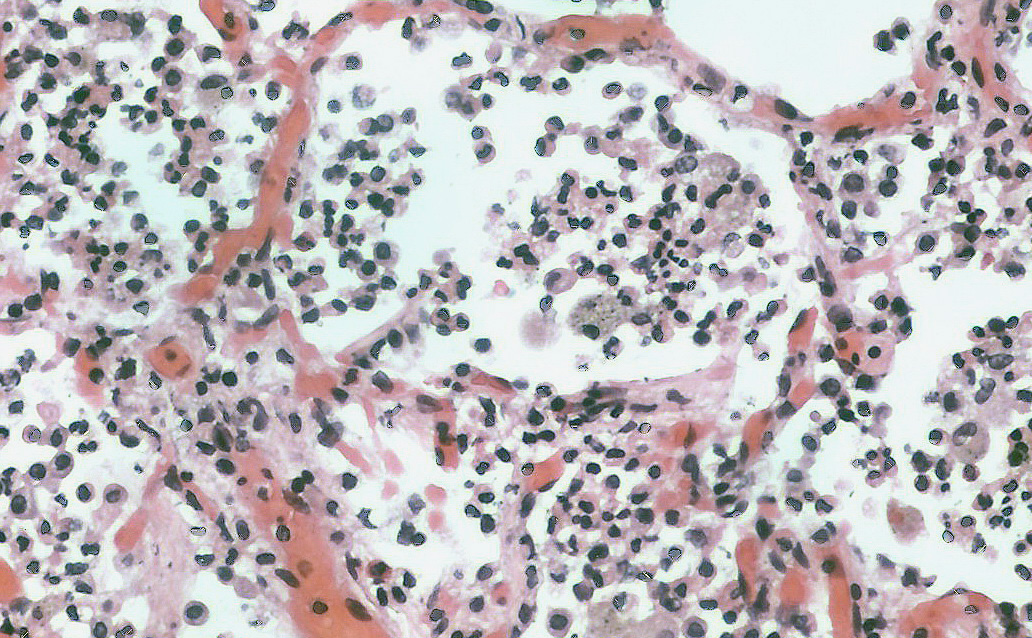

Фотографии бактерий, вызывающих бактериальные пневмонии у животных

Раздел: Другие животные